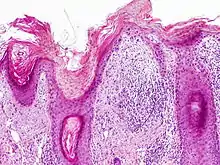

Histopathology

On histologic examination, actinic keratoses usually show a collection of atypical keratinocytes with hyperpigmented or pleomorphic nuclei, extending to the basal layer of the epidermis. A "flag sign" is often described, referring to alternating areas of orthokeratosis and parakeratosis. Epidermal thickening and surrounding areas of sun-damaged skin are often seen.[40] The normal ordered maturation of the keratinocytes is disordered to varying degrees: there may be widening of the intracellular spaces, cytologic atypia such as abnormally large nuclei, and a mild chronic inflammatory infiltrate.[41]

Specific findings depend on the variant and particular lesion characteristics. The seven major histopathologic variants are all characterized by atypical keratinocytic proliferation beginning in the basal layer and confined to the epidermis; they include:[40]

• Hypertrophic: Notable for marked hyperkeratosis, often with evident parakeratosis.[40] Keratinocytes in the stratum malphigii may show a loss of polarity, pleomorphism, and anaplasia.[22] Some irregular downward proliferation into the uppermost dermis may be observed, but does not represent frank invasion.[22]

• Atrophic: With slight hyperkeratosis and overall atrophic changes to the epidermis; the basal layer shows cells with large, hyperchromatic nuclei in close proximity to each other. These cells have been observed to proliferate into the dermis as buds and duct-like structures.[22]

• Lichenoid: Demonstrate a band-like lymphocytic infiltrate in the papillary dermis, directly beneath the dermal-epidermal junction.[40]

• Achantholytic: Intercellular clefts or lacunae in the lowermost epidermal layer that result from anaplastic changes; these produce dyskeratotic cells with disrupted intercellular bridges.

• Bowenoid: This term is controversial and usually refers to full-thickness atypia, microscopically indistinguishable from Bowen's Disease.[22] However most dermatologists and pathologists will use it in reference to tissue samples that are notable for small foci of atypia that involve the full thickness of the epidermis, in the background of a lesion that is otherwise consistent with an AK.[40]

• Epidermolytic: With granular degeneration.[22]

• Pigmented: Show pigmentation in the basal layer of the epidermis, similar to a solar lentigo.[40]